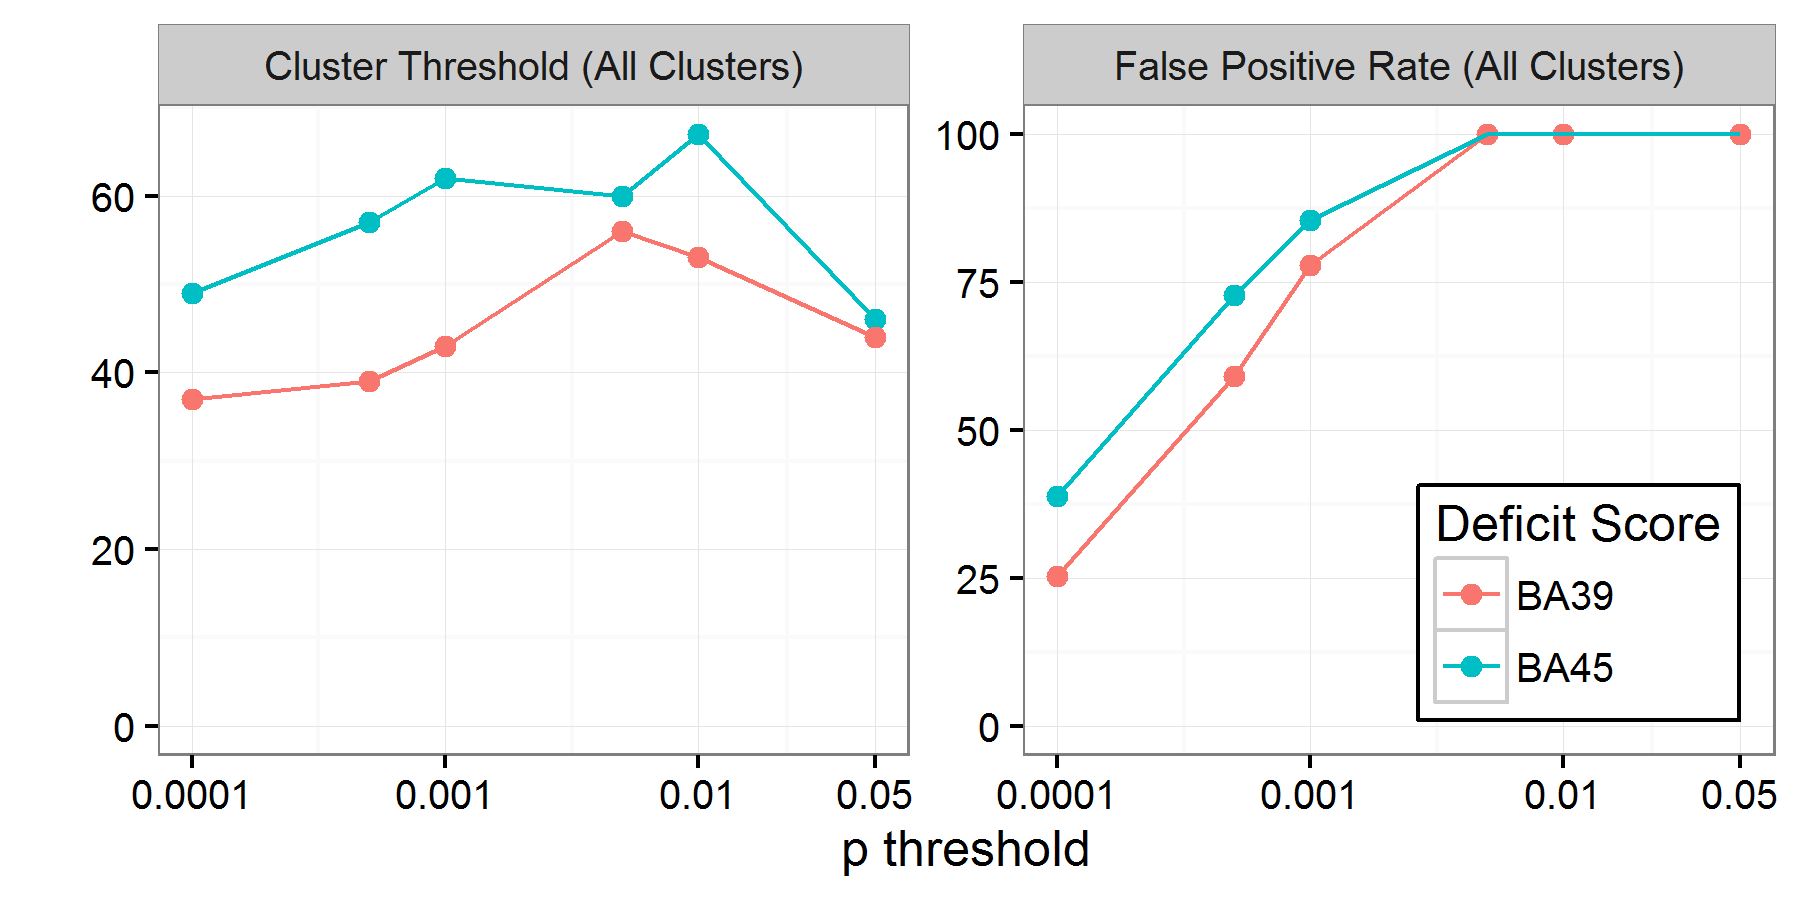

Based on our interpretation of prior work (Pillay et al.,, 2014; Mirman et al., 2015a, ), in our first analysis, all clusters generated by each permutation were entered into the null distribution of cluster sizes for computation of the 95% threshold. The relationship between p-threshold and cluster size threshold is shown in the left panel of Figure 2. Surprisingly, the positive relationship between p-threshold and cluster size threshold was not found – the critical cluster sizes were approximately the same across all p-thresholds. To examine this further, we computed the proportion of permutations that contained at least one cluster larger than the 95% threshold in the left panel of Figure 2. This is measure of false positive rate in the sense that the permutations, by definition, have no systematic relationship between deficit score and lesion location. Therefore, any clusters that survive this correction would be false positives. This false positive rate is shown in the right panel of Figure 2 and was alarmingly high relative to the nominal rate of 5%: it was 25% for the most conservative p-threshold and rose to 100% for thresholds .

This very high rate of false positives is particularly problematic because the cluster size threshold eliminates small clusters, so the false positives that survive this correction will be large and likely to induce unsuspecting researchers to make strong claims about lesion-deficit relationships. This analysis was motivated by reading the method section of Pillay et al., (2014), which had led to a secondary analysis reported by Mirman et al., 2015a , though it is possible that we did not implement their analysis strategy correctly. In their discussion of permutation-based methods for neuroimaging data analysis, Nichols and Holmes, (2002) specified that only the maximum cluster size should be used from each permutation when building the null cluster size distribution, which is analogous to the maximum t-value used for voxel-wise permutation-based correction. In Analysis 2 we re-analyzed the data from the 1000 permutations reported here using only the maximum cluster size.